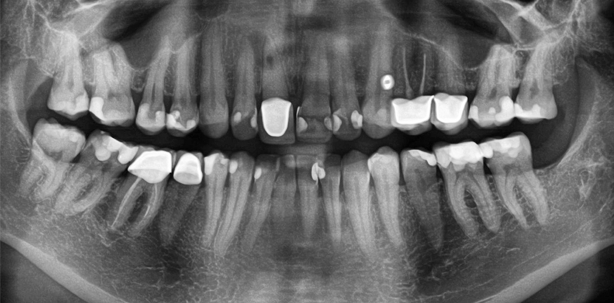

Der Zahn 11 zeigte sich leicht perkussionsempfindlich. Die Taschentiefen betrugen zirkulär 2 mm. Der intraorale Befund zeigte keine Besonderheiten. Die Krone zeigte keine Stufe zirkulär. Der Antagonist berührte die Krone 11 nicht. Einige Röntgenaufnahmen lagen vor: Orthopantomogramm der überweisenden Hauszahnärztin vom 26.9.2013 (Abb. 1), vom 28.1.2014 (Abb. 2, abfotografierte analoge Röntgenaufnahme der Hauszahnärztin) und vom 20.2.2014 (Abb. 3, abfotografierte Röntgenaufnahme der Hauszahnärztin).

Auf den Röntgenaufnahmen zeigte sich eine kreisrunde Aufhellung im Kanalverlauf im Übergang vom mittleren zum apikalen Wurzeldrittel. Es wurde daher beschlossen, ein DVT anzufertigen (Größe 50 mm x 50 mm, Voxellänge 80 μm). Ergebnis: Es zeigte sich eine Diskontinuität im Wurzelverlauf auf der palatinalen Seite. Die Wurzelfüllung war unvollständig sowohl in kaudal-apikaler als auch in horizontaler Richtung. Die Perforation war ungefüllt. Der Knochen war auf der palatinalen Seite fast vollständig resorbiert (Abb. 4).